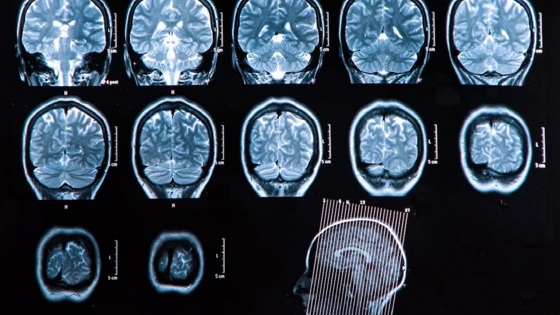

Последние исследования по изучению побочных действий препаратов от болезни Альцгеймера показали, что некоторые из них могут нанести вред здоровью.

К таким относятся препараты, которые ранее называли эволюционными, леканемаба и донанемаба. Первый препарат совместно разработали японская компания Eisai и ее американский партнер Biogen. Донанемаба была разработана американской компанией Lilly.

Как оказалось, они могут привести к уменьшению объемов мозга, а также кровотечениям, сообщает The Times.

Правда, исследования показали, что они могут очистить мозг от токсичного белка амилоида, который считается отличительным признаком болезни Альцгеймера.